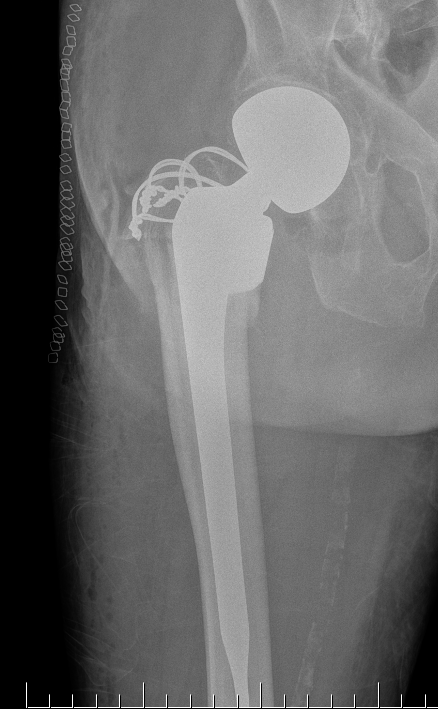

Hemiarthroplasty / Total hip replacement

Indications

- severe comminution

- salvage of failure of previous fixation

Technical

- may need calcar replacement

- may need greater trochanter fixation

THA Issues

A. Femoral component

- cement will come out screw holes

- Option 1: leave screws in laterally, and strip medially to insert small screws

- Option 2: use uncemented stem

B. Length of femoral stem

- should bypass distal screw hole by 2 cortical diameters

C. Calcar

- normal stem usually sufficient if LT healed back on

- otherwise may calcar replacing

D. Greater trochanter

- may need plate / cables to reduce